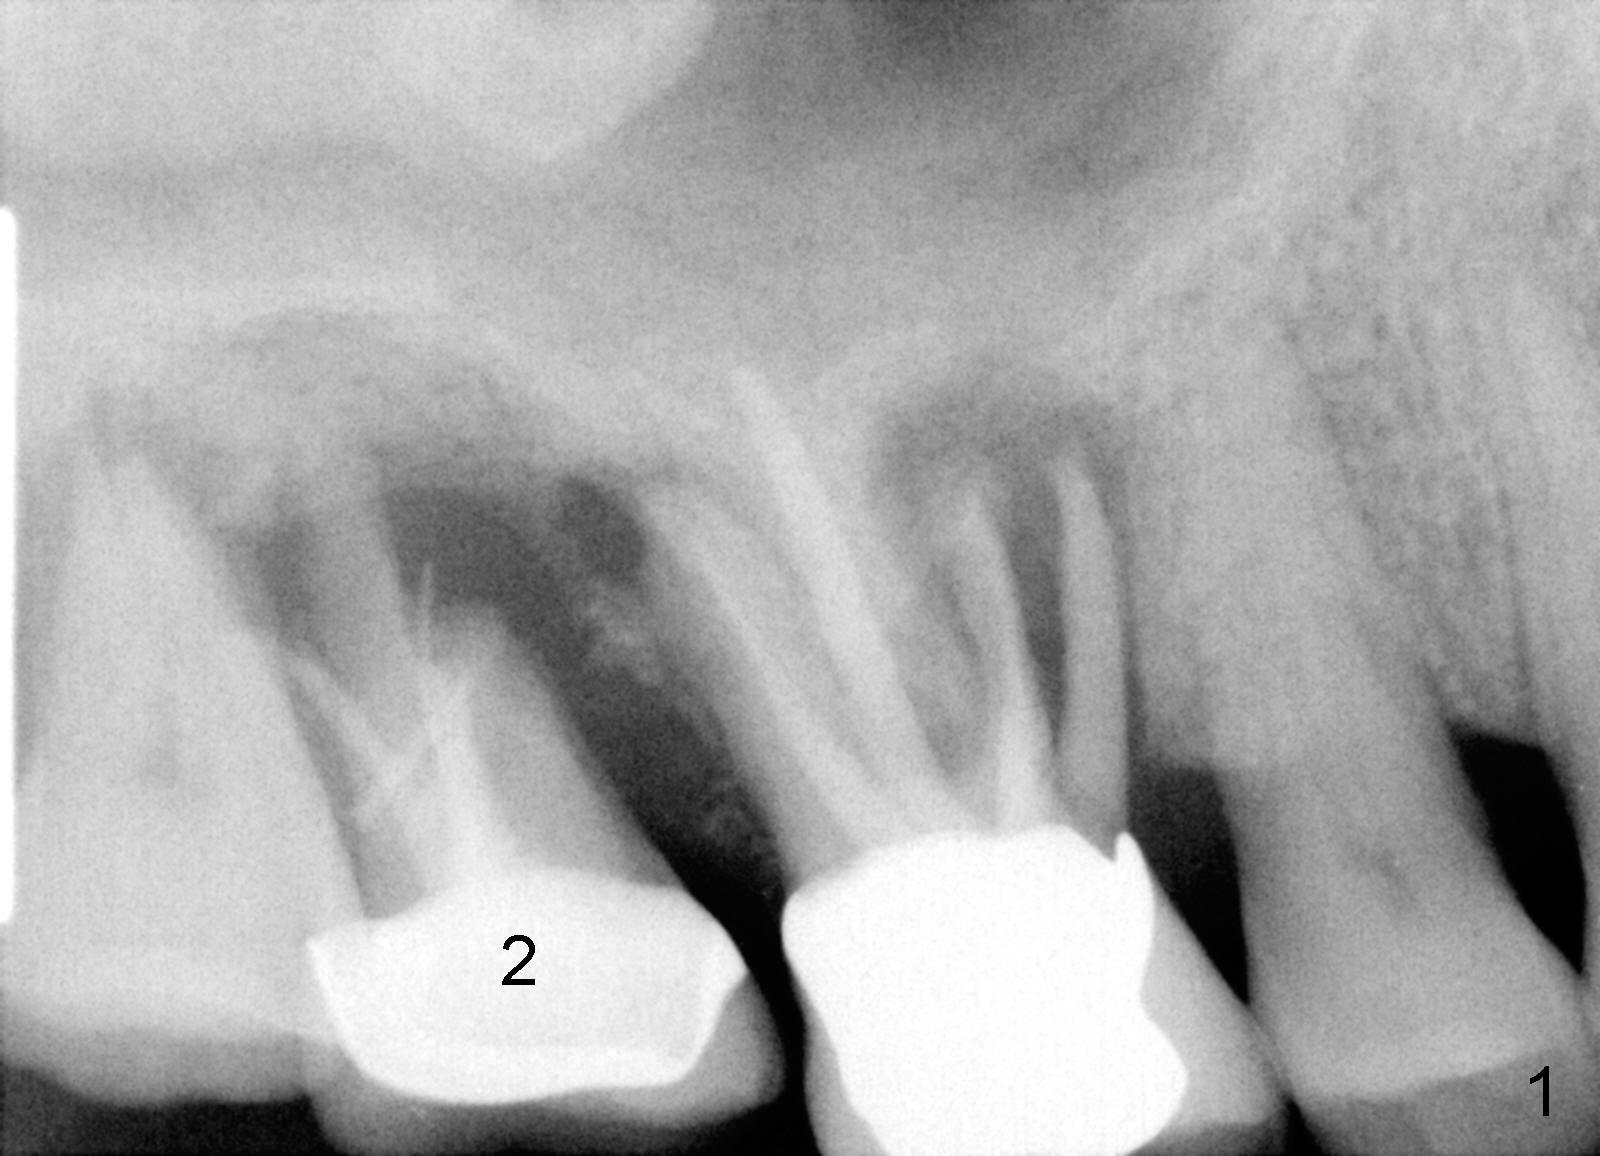

The 60-year-old man is a bruxer. All of the three upper right molars are nonsalvageable (Fig.1). Since #2 is symptomatic, it is planned to be extracted and restored first. As expected, there is severe alveolar destruction (single large socket), while the base bone is solid. A series of tapered osteotomes (2-5 mm) are used to create osteotomy in the base bone (gaining 4 mm into new bone), followed by 4.5x20 mm tap at the depth of 17 mm from the gingival margin (Fig.2). Then the depth is adjusted to 14 mm; the bone expansion and osteotomy continue until using 7 mm tap with good binding to the bone (Fig.3). A 7x14 mm implant is placed with insertion torque more than 60 Ncm (Fig.4). No bone graft is used for sinus lift considering sinus membrane perforation. The buccal flap is raised to reveal bony defect, which is covered by Osteogen (a synthetic bone graft) and then collagen membrane (Fig.6 *). Five days postop, the membrane undergoes a type of transformation (Fig.7 *) leading to a gingival tissue (Fig.8 *, 18 days postop). By 3 months, the gingiva has normal appearance (Fig.9), while the implant seems to be osteointegrated (Fig.10). Once the infected source is removed, our body has potential to regenerate.